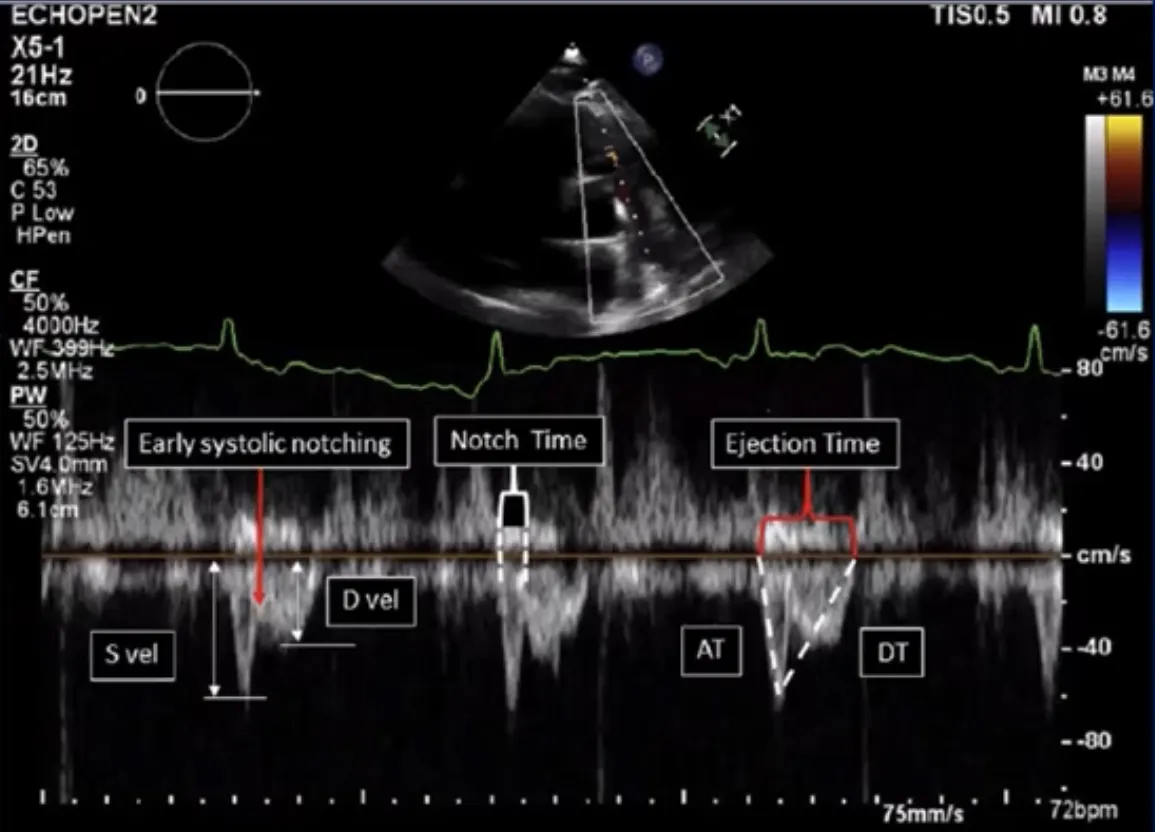

B1. PA Early Systolic notching

PSX view 에서 Aortic valve 와 PV 가 보이는 view를 잡고 PW doppler 적용

segmental/subsegmental PE제외 시 민감도, 특이도 모두 90% 이상, AUC 0.96

Suggests a proximally-located, higher-risk PE

From a technical perspective, the PV’s opening click on the PA systolic ejection waveform can be a false-positive for ESN